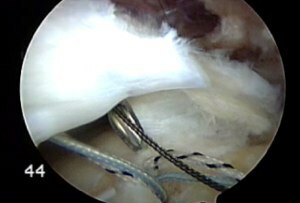

回旋腱板断裂は、すべての年齢の人々にとてもよく見られる傷害です。読む論文にもよりますが、50歳以上で13%の人が、80歳以上で50%の人が回旋腱板断裂を患っているだろうと報告されています。自然の成り行きとして、回旋腱板修復手術も同様によく見られるようになってきています。過去数十年で、我々は、回旋腱板修復手術技術を大きく進歩させ、直視下手術から、より低侵襲な“開口部の小さい”手術、そして、完全関節鏡視下手術へと発展させてきました。